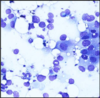

what does malignant aspiarates look like?

- high cellularity

- crowding/overlapping of cells

- loss of cohesion (resulting is dissociated isngle cells)

- nuclear pleomorphism (larger nuclei and varrying shape)

- hyperchromasia (nuclei look dark - A morphologic finding referring to the presence of darkly stained nuclei due to abundance of DNA on hematoxylin-eosin stained sections. It is suggestive of malignancy.)

- absence of bipolar nuclei